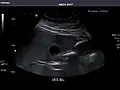

Abdominal Ultrasound (Full Exam)

STRUCTURED REPORT

(Technique: Transabdominal ultrasonography; Device: Toshiba Aplio XG)

Liver: Diffusely homogeneous and normal in echogenicity. No focal mass or contour nodularity. No intrahepatic biliary ductal dilatation.

Portal Vein: Patent main portal vein.

Gallbladder: No stones, wall thickening, or pericholecystic fluid.

Common Bile Duct: Nondilated measuring 1.3 mm at the level of the porta hepatis.

Pancreas: Visualized portions unremarkable.

Spleen: Normal in size.

Kidneys: Right and left kidneys measure 11.5 cm and 12 cm in length respectively. No hydronephrosis. Small left lower pole kidney cyst.

Ascites: None.

Aorta: Visualized portions normal in caliber, 16 x 15 mm.

IVC: Normal.

IMPRESSION:

Normal abdominal ultrasound.